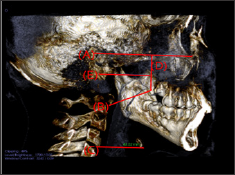

In order to quantitatively evaluate the effects of orthopedic treatment, finite element analysis was performed using a skull model from 3B Scientific® Biologia was scanned. For the comparison with the clinical results, the skull was set to the approximately same size of children's head of 8.3 years old. RAMPA was designed as the 3-dimensional structure in Solidworks™ as shown in (Figure1a). After combining the skull with RAMPA, they were imported to ANSYS Workbench. The materials were used for the finite element analysis and the values of mechanical properties were utilized from the previous study [19] as listed in (Table 1). In addition, a number of assumptions were made as follows;

Figure 1: RAMPA; a, Actual RAMPA installed on a skull model; b, RAMPA modelling for finite element analysis F1, The horizontal force F2, The front-vertical force F3, The rear-vertical force.

The results were shown for palatine bone at the points called the landmarks as in (Figures 4-8), which were used as in the previous orthodontics researches [20-22] for reliable data analysis. The results for the marked points (A, B, C, D, and E) of the midpalatal plane are shown in (Table 2). The 3-dimensional coordinates are X, transverse plane; Y, sagittal plane; Z, vertical plane.In the transverse plane, the midpalatal suture had the maximum displacement at the most front (point A) and was deformed in the opening direction, but the differences were little. This is also because of contraction of the palate from the forces exerted by RAMPA. In the sagittal plane, all midpalatal suture points showed forward movement, but the differences were little. Vertically, all of them had upward movement, which shows the antero superior protraction from RAMPA. For the results of the alveolar bone from midpalatal expansion, the displacement became larger in the posterior than in the anterior areas in the transverse plane, but the differences were little. This is because the external force exerted by RAMPA has the effect of tightening the dental arch of the palate. Sagittally, larger displacements occurred forward at the incisors, the canines, and the premolars were displaced forward. Vertically, the alveolar bone at teeth around molars was intruded, which was due to the upward force applied from RAMPA. (Figure 5) shows the Z-directional displacement distribution for the upper maxillary bones.

Figure 4: Important points for analyzing displacements and stresses; A, Point near the incisive foramen; E,point near the palatine bone; B, C, D points divide the A-E line into 4 quarters.